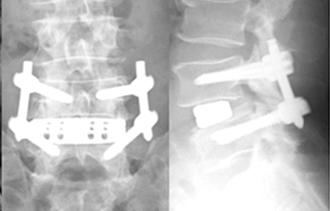

側方経路腰椎椎体間固定術(LLIF)

対象となる疾患は、腰椎椎間板ヘルニア、腰部脊柱管狭窄症、腰椎変性すべり症、一部の腰椎分離すべり症、腰椎変性側弯症、腰椎後弯症などです。原則、手術翌日より硬性のコルセットを装着し、起立・歩行を開始します。LLIFは、日本では2013年から承認され実施されており、普及しつつある低侵襲な手術法です。XLIF(エックスリフ)は全国でも限られた医師と医療機関でのみ実施されています。当院では、実施許可を取得した医師により施行され、多くの実績があります。類似した術式にOLIF(オーリフ)などもあります。手術では側腹部に約4cmの傷で手術を実施します。この手技の利点は、関節除圧と言って神経を直接触らないで神経を圧迫から解除できることや、大きな椎間スペーサーを挿入することによる変形の矯正や安定したサポートを得られることです。

第4腰椎に著明なすべりを認め、重度の狭窄を認めます。 -

側方経路腰椎椎体間固定術(LLIF) 椎間板に大きなスペーサーが挿入され、また経皮的に椎弓根スクリューの挿入とロッドの連結がなされ、第4腰椎のすべりが矯正され固定されています。